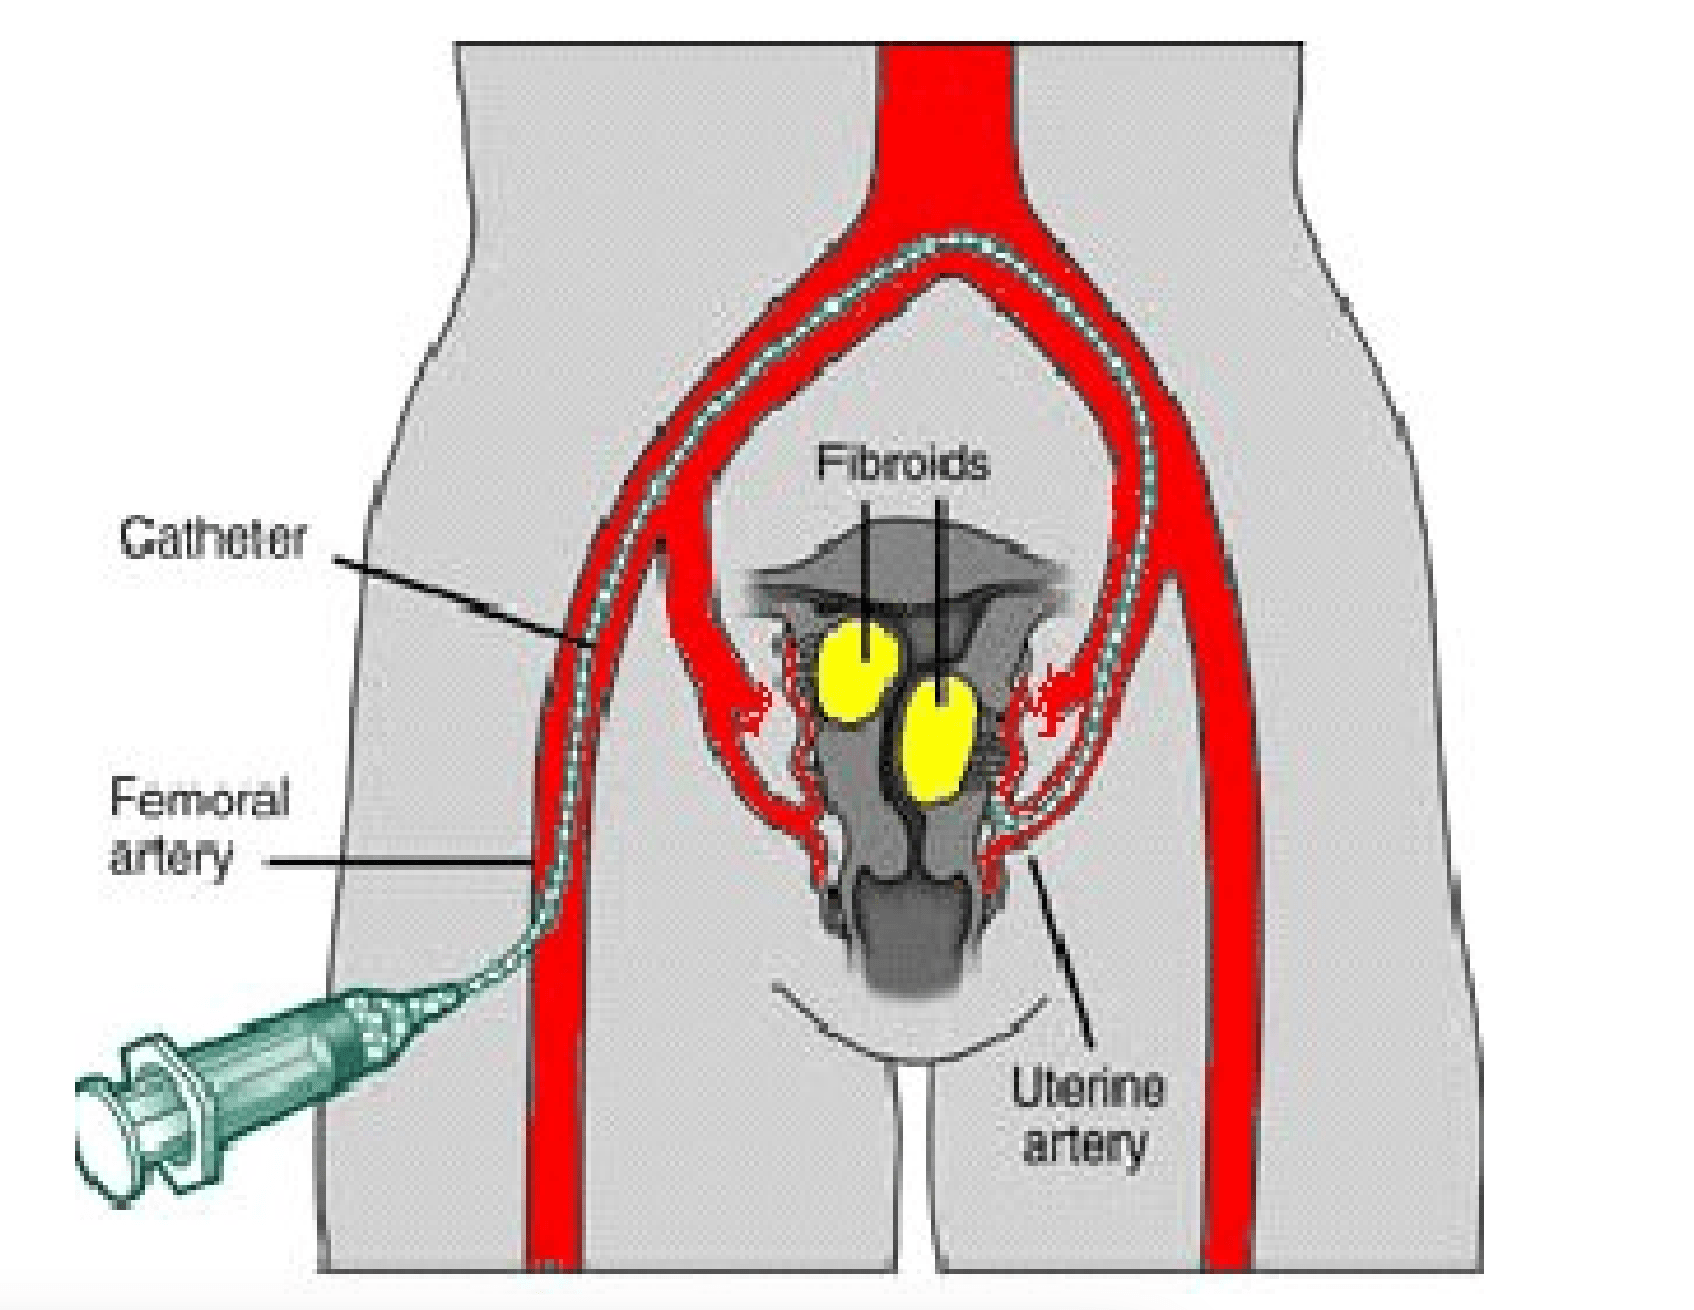

Is University Hospital Frankfurt suitable for patients with cancer?

It is one of the largest institutions dealing with cancer treatment. The oncology unit has a spiral tomograph, a gamma knife, PET, and other latest-generation equipment. Moreover, the team has performed hundreds of successful operations to treat the most complex oncological diseases.